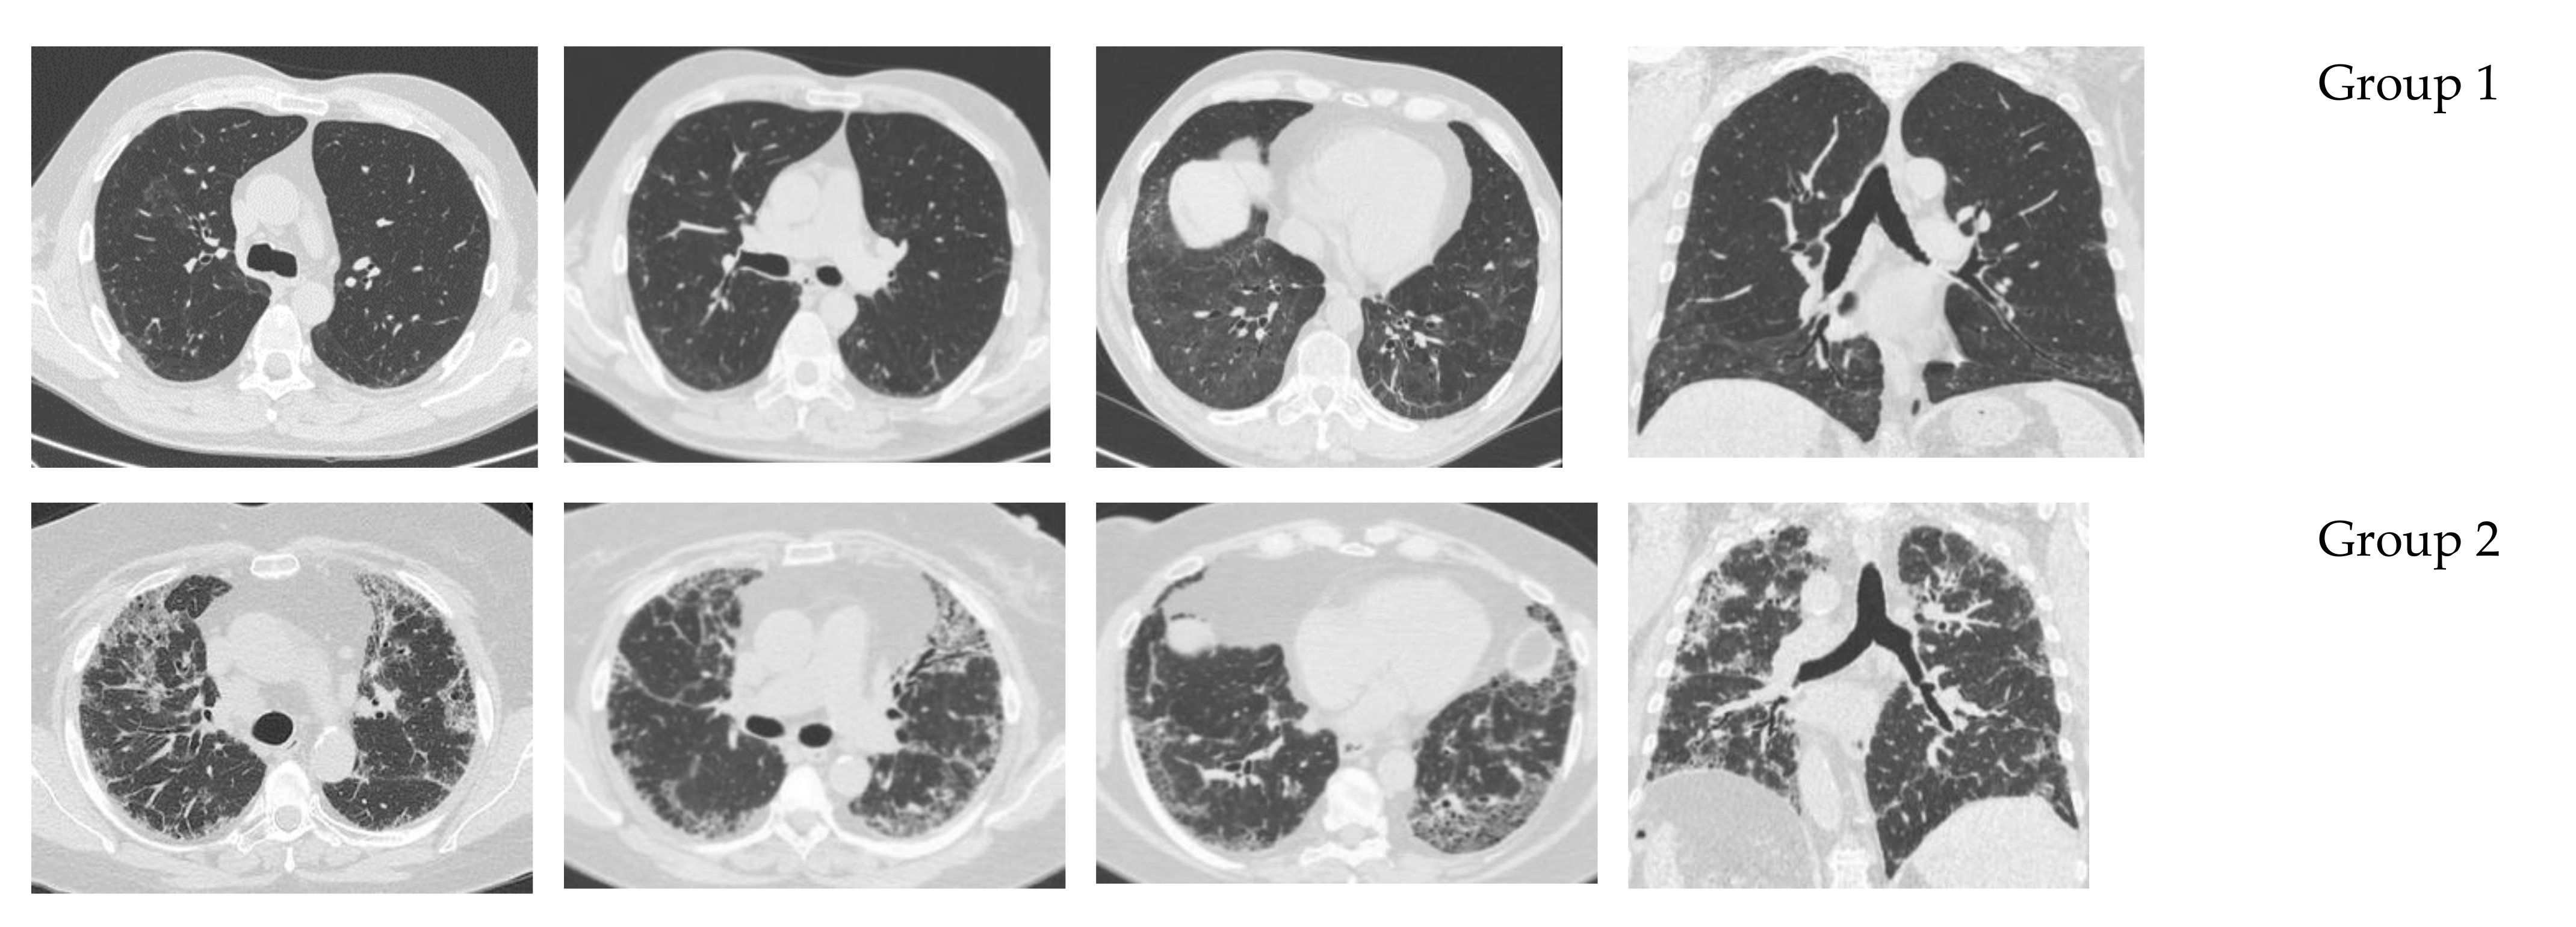

| Lung HRCT and function | ||||

| 5.8 ± 1.9 67 ± 5 56 ± 14 | 7.6 ± 2.3 78 ± 20 75 ± 25 | 0.0398 0.001142 0.008410 |